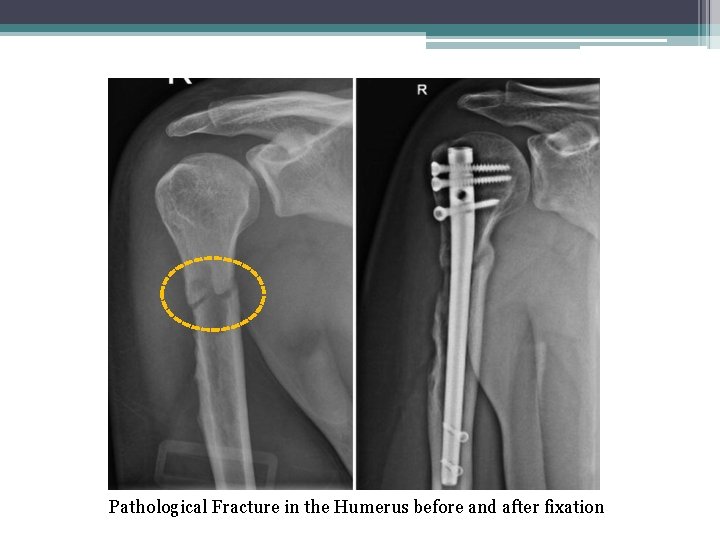

• 4 -Pathological Fracture: Bone fracture caused by an underlying disease/condition that weakened the bone). Pathological Fracture in the neck of the humeurs Pthological Fracture in the femur

Pathological Fracture in the Humerus before and after fixation